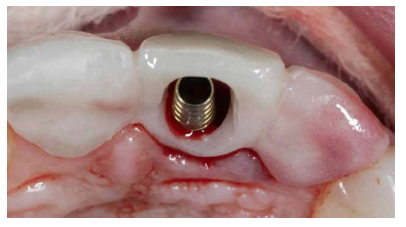

Caso clínico: Se presenta el caso de una paciente mujer de 32 años de edad, que acude por presentar una posible fractura radicular del incisivo central superior izquierdo (ICSI), acompañada de la aparición de un absceso periodontal en la región del fondo de vestíbulo de dicho diente. Tras llevar a cabo la exploración clínica y radiológica, se establece que el pronóstico del ICSI es desfavorable para llevar a cabo un tratamiento conservador del mismo. Tras la valoración de las características clínicas del caso presente, el plan de tratamiento se inclinó por la realización de la exodoncia del ICSI con la colocación simultánea de un IOI postextracción y la carga inmediata con una prótesis provisional del mismo.

Clinical case: We present the case of a 32-year-old female patient who presented with a possible root fracture of the upper left central incisor (ULCI), accompanied by the appearance of a periodontal abscess in the region of the bottom of the vestibule of said tooth. After carrying out the clinical and radiological examination, it is established that the ULCI prognosis is unfavourable for carrying out conservative treatment of the tooth. After assessing the clinical characteristics of the present case, the chosen treatment plan was to extract the ULCI with the simultaneous placement of a post-extraction osseointegrated implant (OII) and immediate loading of a provisional prosthesis on the implant.

Los beneficios de la carga inmediata incluyen una reducción notable de las intervenciones quirúrgicas, una menor dilatación temporal del tratamiento e incluso un mejor bienestar psicológico y social para el paciente. En casos con importante compromiso estético, la carga inmediata o la provisionalización inmediata, añadida a la colocación inmediata postextracción del IOI permiten minimizar las alteraciones derivadas de la pérdida dental, manteniendo el perfil de emergencia, contorno de tejidos blandos y las papilas gingivales5-7.

Así mismo, se han establecido diferentes protocolos para el manejo del sector estético anterosuperior, que se suman al acto de la colocación inmediata del implante y la corona provisional, donde se incluyen la colocación de un material no reabsorbible entre el IOI y la cortical vestibular para minimizar el posible colapso, así como el manejo de los tejidos blandos periimplantarios8-11.